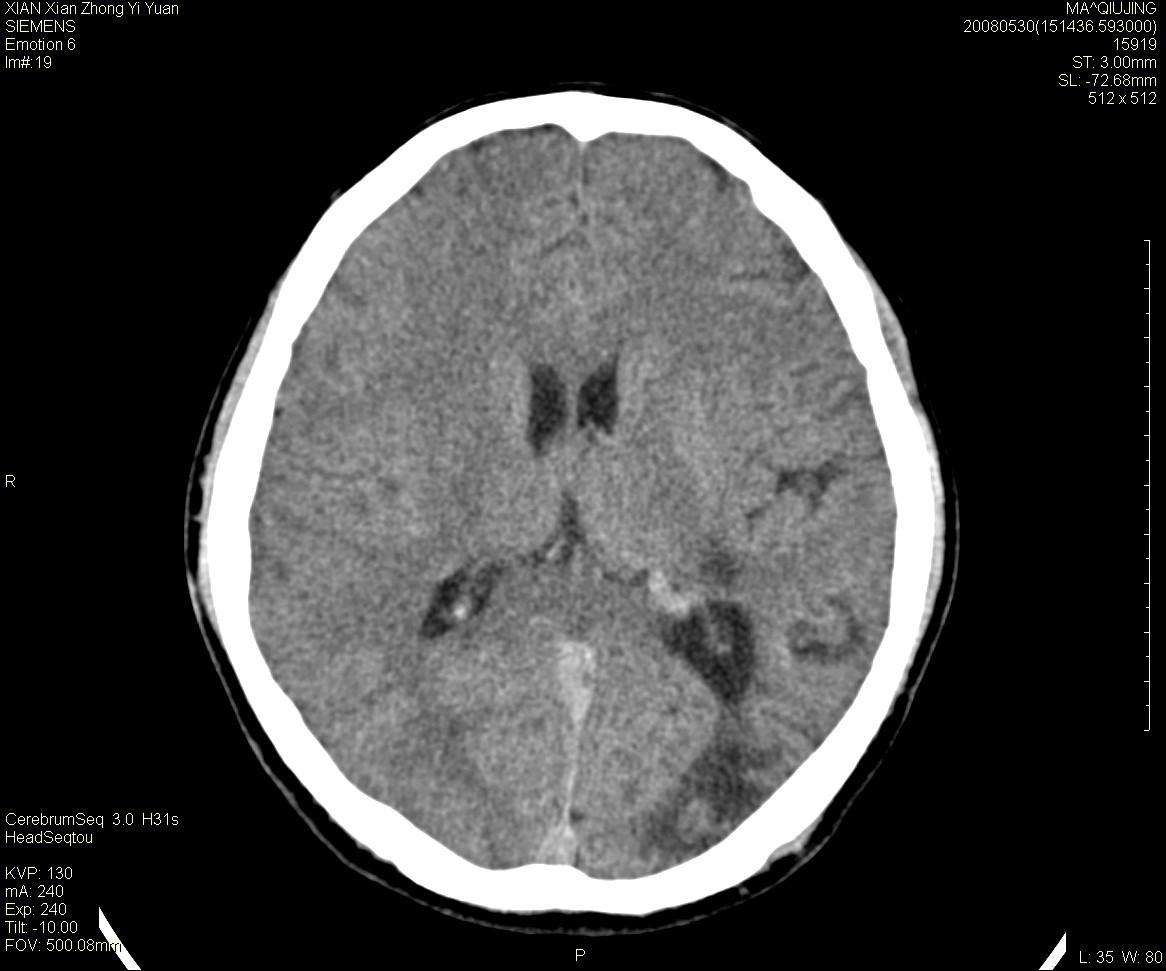

标题: CT13768:少见病例,血管畸形。

患者m47,头晕数年,没给强化,让做dsa去了。

avm

第一感觉:avm,但其中更低密度区不清楚,好像有脂肪密度,胆脂瘤破裂?

avm,低密度区应该是以前出血过的液化灶

血管畸形,支持,如果增强扫描,则可见粗大,迂曲血管团。